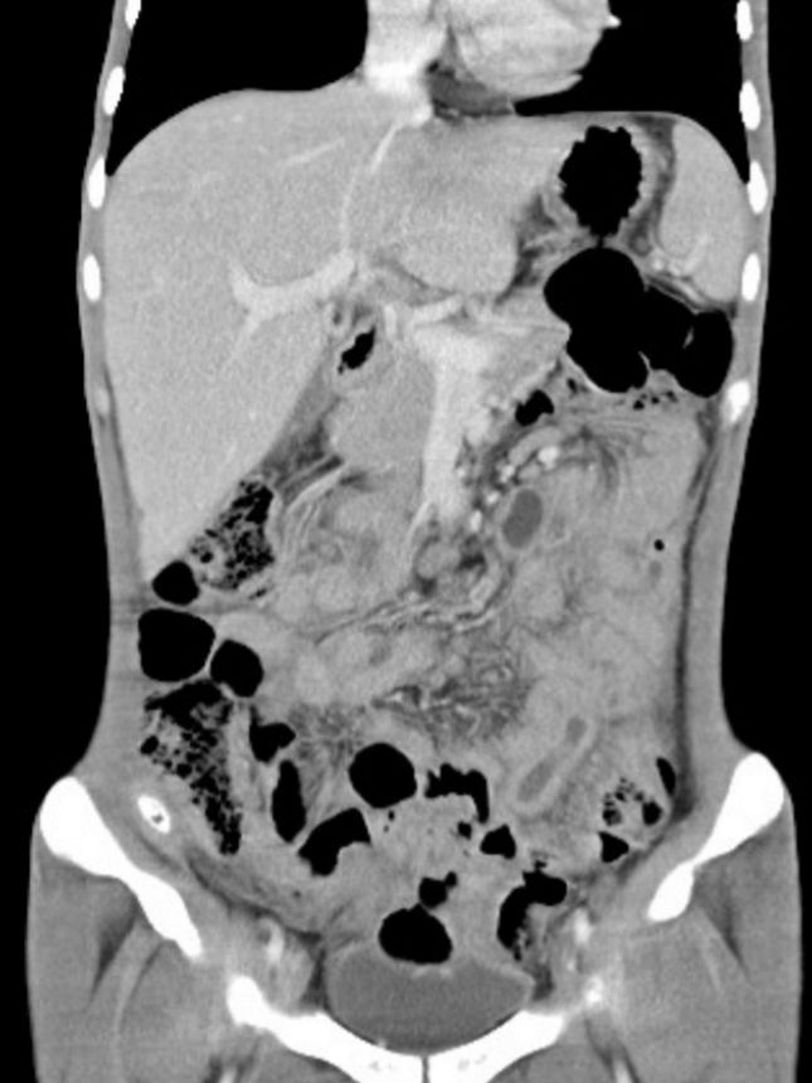

Hello. What is the diagnosis . 21old male , symptoms: weight loss, poor appetite, abdominal cramping and diarrhea

Crohn

It could be diverticulitis

TB

It Can be Intestinal TB Deverticulosis HIV AIDS